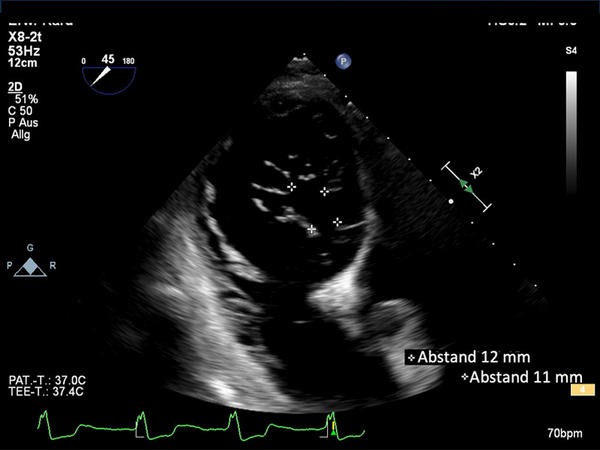

Transösophageales Echokardiografie

Der transgastrische Blick zeigt die schwere Koaptationslücke mit zwei großen Insuffizienzjets anteroseptal und posteroseptal.

Visualisierung der großen Koaptationslücken anteroseptal (11mm) und posteroseptal (12mm) im transgastrischen Blick